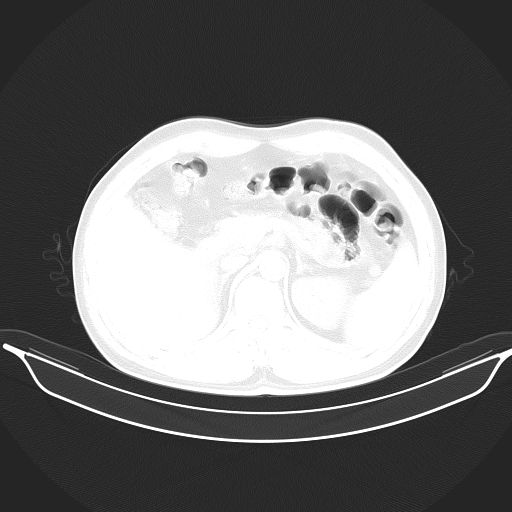

标题: CT25490:男,40岁,体检发现;无其它不适。 [打印本页]

标题: CT25490:男,40岁,体检发现;无其它不适。

考虑:1、过各敏性肺炎可能性大,建议定期复查。

2、轻度脂肪肝。